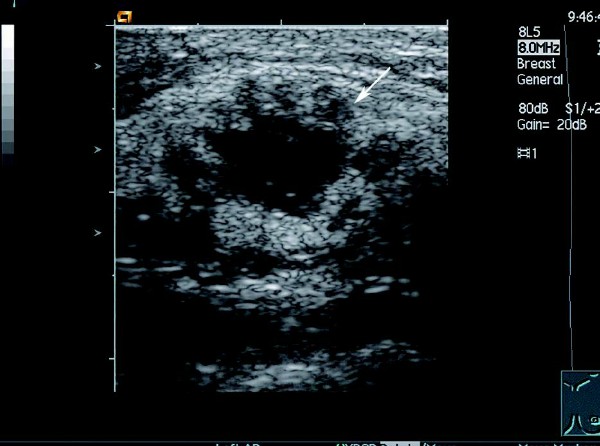

乳腺癌的超声图像表现,早期乳腺癌的超声表现 4. 部分肿块边缘可出现“恶性晕”征,表现为肿块前壁和侧壁不规则、厚薄不均的强回声带包绕,厚度约 1~3 mm

5.CDFI 显示肿块周边及内部血流信号增多,并有新生血管及动-静脉瘘形成,内见穿支动脉血流,形成高速高阻及动静脉混叠现象。

患者,女,46岁。查体时发现右乳腺一肿物,活动度差,质硬。超声检查报告显示:右侧乳腺外上下象限乳腺边缘可见一大小约1.5 cm×1.2cm的偏低回声团,边界不清晰,形态不规则,包膜不明显。内部回声不均匀,可见少量沙砾样强回声点,纵横比>1,偏低回声团后方衰减明显。CDFI:其内可见短管样血流信息,动脉可见高速,高阻血流信息。

超声提示:右侧乳腺实质性肿块伴钙化,考虑乳腺癌